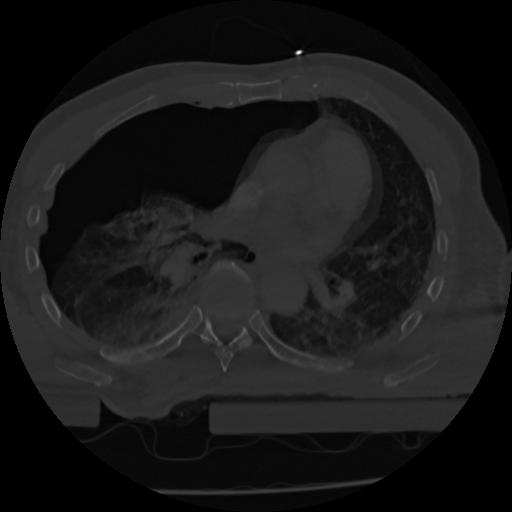

22 ANGIO,CE,Vol,0.5,ANGIO,,